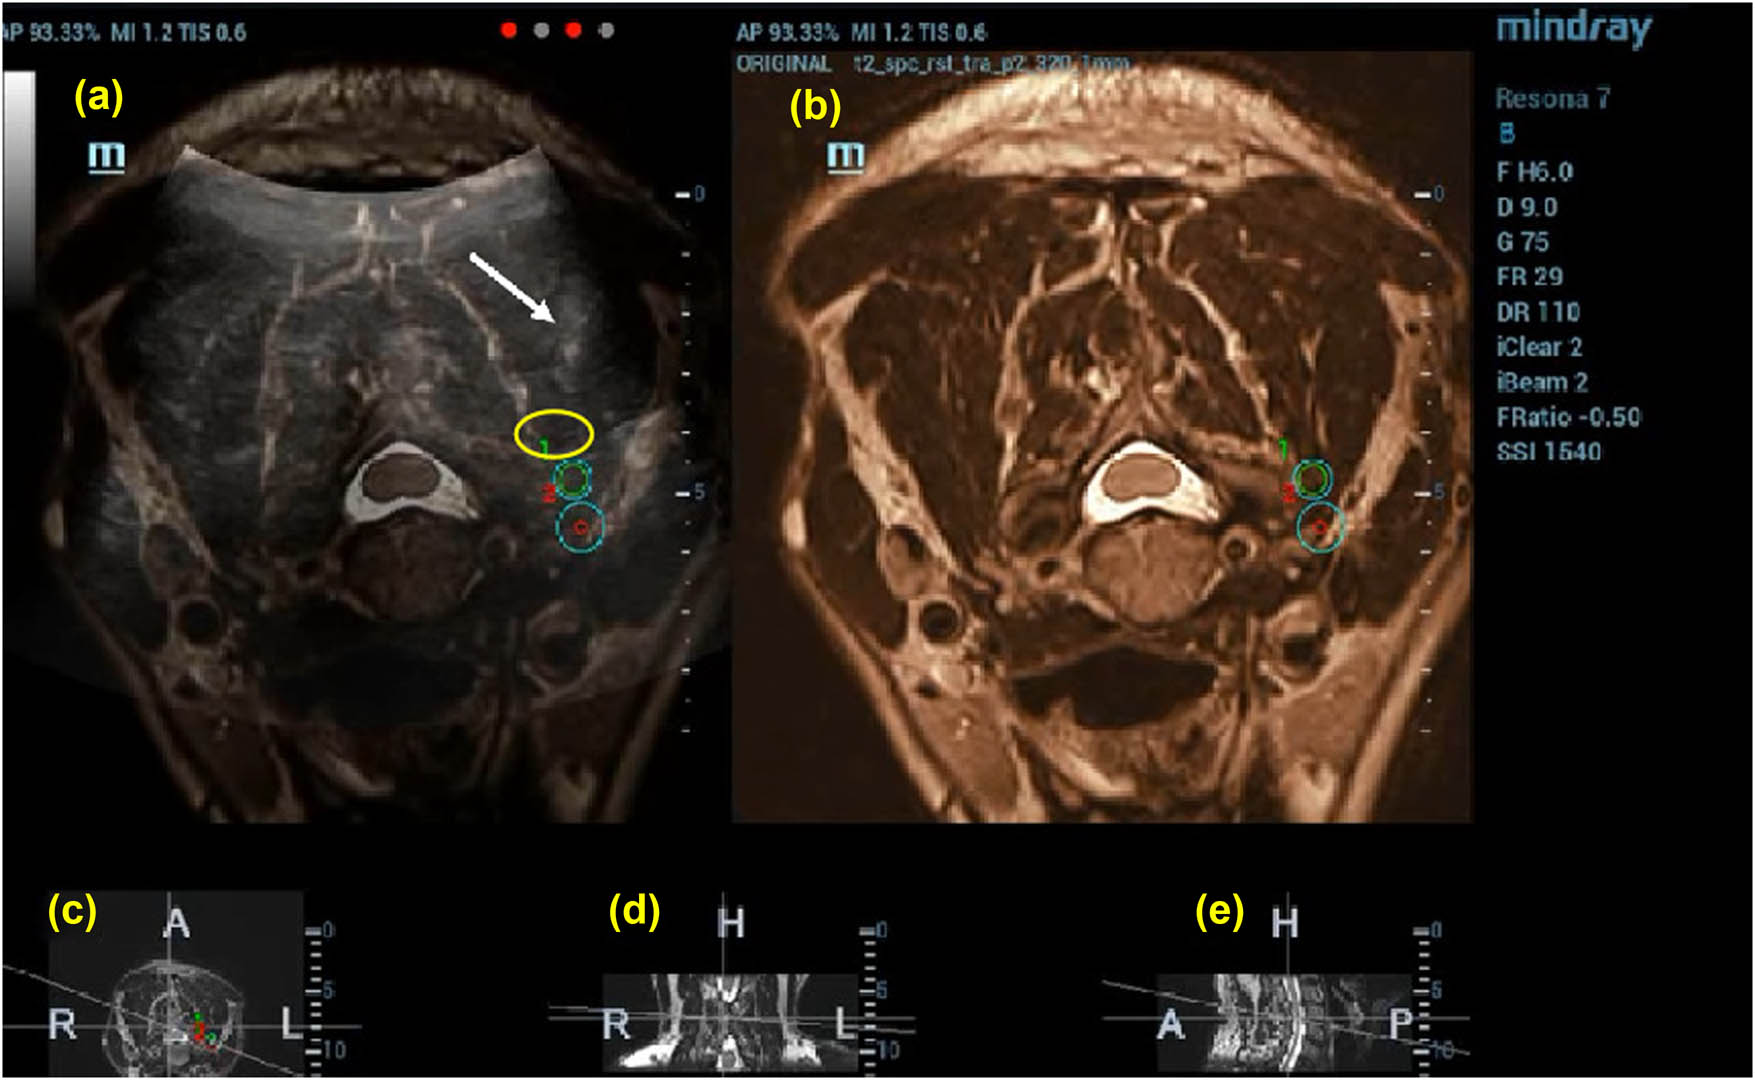

Once the needle was accurately positioned, ensuring no blood, fluid, or gas was aspirated, the therapeutic medication was administered. The spread of the therapeutic agent was monitored in real-time via US, observing its diffusion around the target area (Figure 3).

Puncture to preset target 1 guided by US (50%)-MRI (50%) image. The drug solution is injected after the puncture is guided by US (50%)-nuclear magnetic resonance (50%) image; the white arrow indicates the location of the puncture needle and the yellow circle indicates the solutions diffusion range. (a) US-MRI fusion images, with green circles indicating the target puncture points, (b)MRI images, (c) cross section, (d) coronal section, and (e) sagittal section.